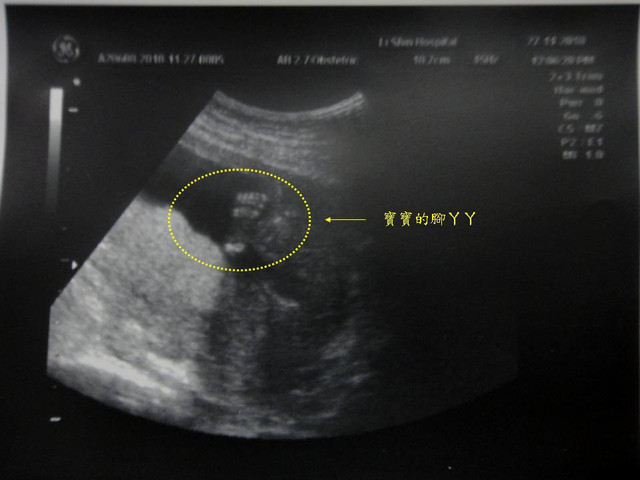

當天,我家小荳荳很配合醫生叔叔進行檢查,

重要時刻開獎囉!呵!我們是美美的小公主,讚唷!